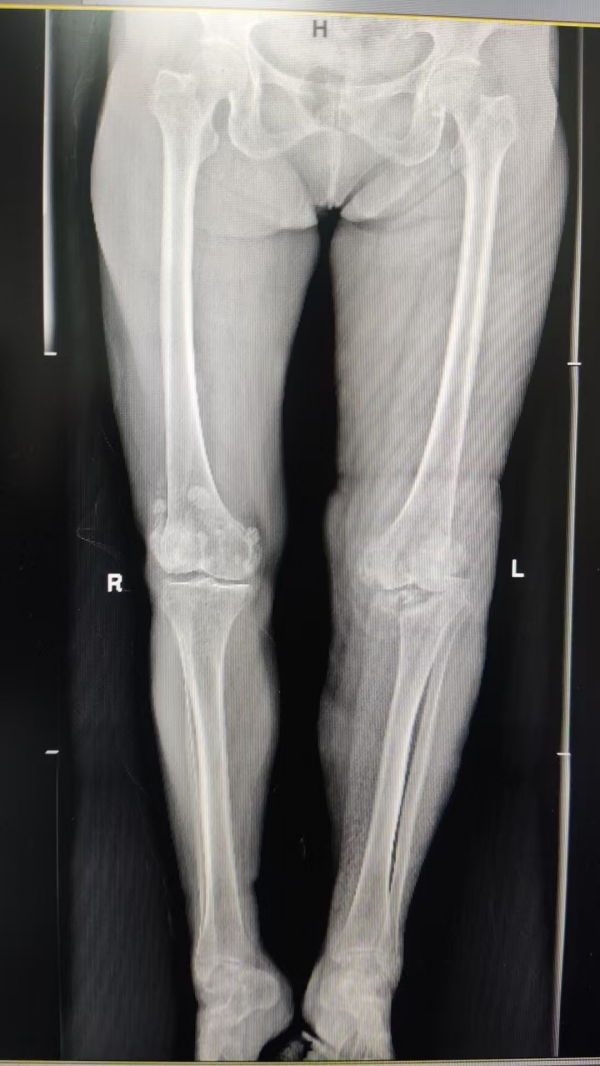

▲术前

该患者长期饱受膝关节剧痛和活动受限困扰,生活质量严重下降。入院后经系统检查,确诊为梅毒性膝关节炎。此病本就罕见,加之患者膝关节已遭严重破坏,传统疗法难以奏效,关节置换成为唯一有效选择。然而,患者合并梅毒感染的特殊情况,使得手术面临极高的感染风险、复杂的免疫反应等难题,且国内外可借鉴的成功案例极为有限。面对如此复杂的病情,我院骨关节科迅速启动多学科会诊,联合院内皮肤科、感染科、检验科、麻醉科专家,并特邀四川大学华西医院专家进行远程会诊。团队深入研讨病情,整合各学科优势,为患者量身定制了精准的治疗方案。